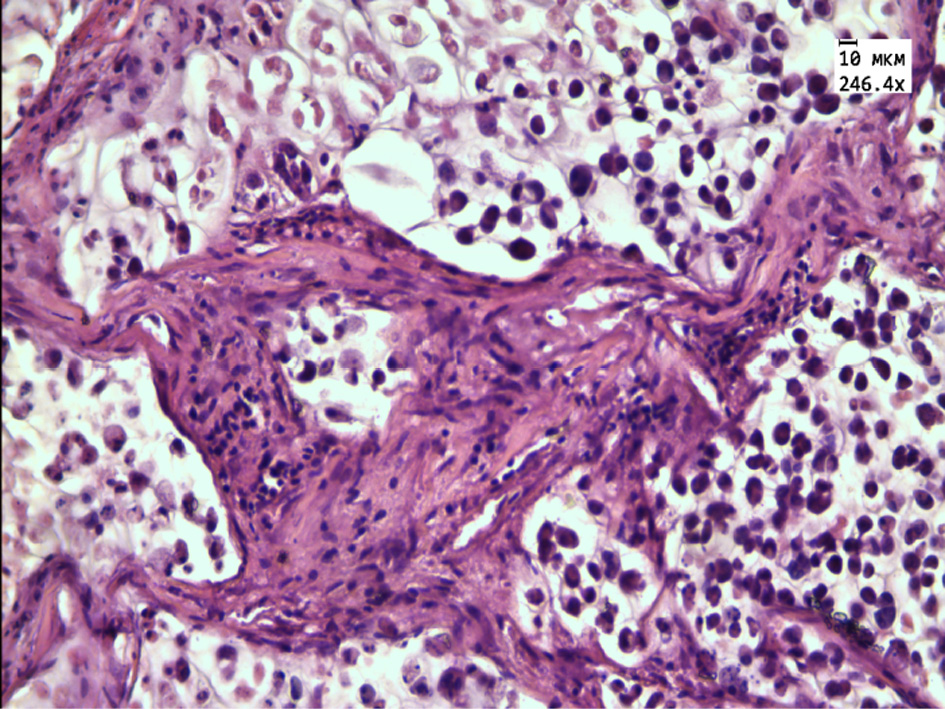

The morphological examination revealed that the transplanted tumor in the control group consisted of cellular structures of different shapes and sizes, separated by thin layers of connective tissue (Fig. 1). Tumor cells of oval or rounded shape, in the cytoplasm are large vacuoles containing mucus and pushing the oval nucleus to the periphery of the cell. The number of mitoses was 6 in one visual field. Single tumor cells of necrosis were noted.

Figure 1 – Histological tumor structure of the control group

Note: the tumor cells are separated by thin layers of connective tissue. Stained with hematoxylin and eosin. Magnification 246.4×.